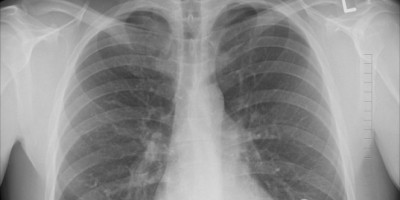

Ono što je danas poznato kao covid-19, označavao se krajem 2019. kao skup slučajeva upale pluća nepoznatog uzroka, navodi "Gardijan". Kasnije se ispostavilo da je u pitanju teški akutni respiratorni sindrom, koji izaziva Sars-CoV-2 virus, odnosno pomenuti covid-19.

Kako se covid-19 razvija u tešku upalu pluća, kakve posledica ostavlja na plućima i na ostale delove organizma?

Kako se razvija upala pluća?

Kada oboleli od covida-19 imaju povišenu temperaturu ili ih muči kašalj, dr Vilson kaže da je to posledica infekcije koja dopire do respiratornog stabla - vazdušnih puteva koji dovode vazduh do pluća.

Kada se naruši obloga respiratornog stabla, dolazi do upale, iritacije nerava u sluznici disajnih puteva (Iritiaciju može da izazove i najmanja čestica prašine).

Ukoliko se stanje pogorša, infekcija dopire do obloga disajnog puta i do jedinica za razmenu inspiratornog gasa. Ako se i one upale, izlučuju upalne materije u vazdušne vrećice koje se nalaze na dnu pluća.

U slučaju da dođe do upale tih vrećica, štetan materijal - tečnosti i upalne ćelije, dolaze do pluća i javlja se pneumonija.

Dr Vilson napominje da pluća koja su puna upalnim materijalnom ne mogu da oslobode dovoljno kiseonika u krvotok, smanjuju sposobnost organizma da preruzme potrebne količine kiseonika i oslobodi ugljen-dioksid.

"To je uobičajeni uzrok smrti teške pneumonije", rekao je doktor.

Da li se pneumonija koja prati Covid- 19 razlikuje od uobičajene upale pluća? Stručnjaci daju potvrdan odgovor na ovo pitanje. Uobičajena upala pluća je bakterijska i leči se antibioticima. I zahvata samo delove ovog organa, dok pneumonija koju izaziva Covid- 19 obuhvata cela pluća.